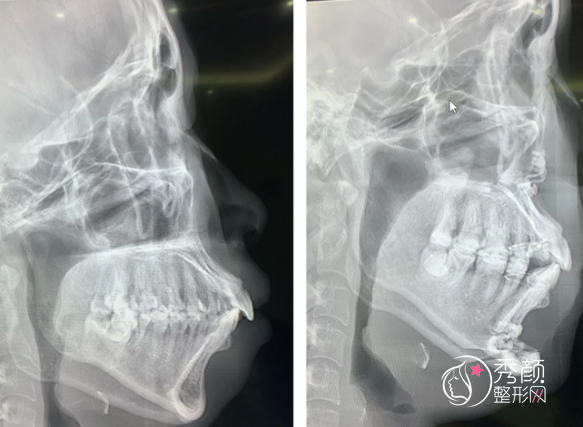

正颌手术医保可以报销吗?正颌手术一般费用是多少钱?

正颌手术医保可以报销吗?哪些地方可以报销?正颌手术一般需要多少钱?贵不贵呢?首先得明确,正颌手术在大部分情况下属于整形美容范畴,但在某些特定情形下,又与医疗功能性恢复紧密相连,这就让医保报销政策在各地有不同的情况。

关于正颌手术的费用,其受多种因素影响,整体范围在2万元至20万元之间,具体取决于手术类型、病情严重程度、医疗机构选择及地区差异等.